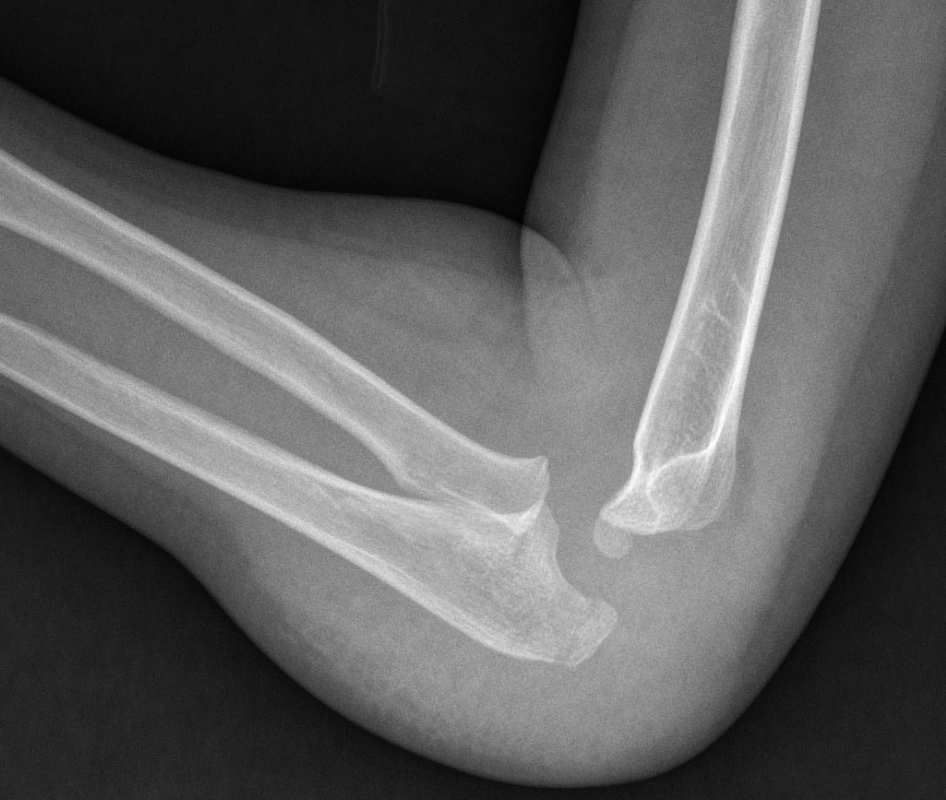

Le fratture metafisarie di olecrano (Figg. 1, 2) invece sono più frequenti, legate a tre meccanismi diversi:

- Traumi diretti a gomito flesso

In queste fratture accade che la forza tricipitale prossimale e la forza del muscolo brachiale distale aumentino la suscettibilità della corticale olecranica posteriore che quindi facilmente si rompe con linee fratturative trasverse intrarticolari.

- Traumi a gomito esteso con stress in varo o valgo

In accrescimento è frequente trovare una condizione di iperlassità legamentosa che, in caso di traumi a gomito esteso, favorisce lo sviluppo di fratture sovracondiloidee. L’olecrano distale può essere interessato quando il gomito oltre ad essere iperesteso è anche stressato in varo o valgo. Si tratta di fratture tipicamente lineari ed extrarticolari, a “legno verde”.

- Traumi con fratture da forza di taglio

Si tratta di fratture rare, generate da traumi diretti all’olecrano che causano una forza di trazione anteriore, a seguito della quale il frammento distale si disloca anteriormente. La rima di frattura può essere trasversa o obliqua.